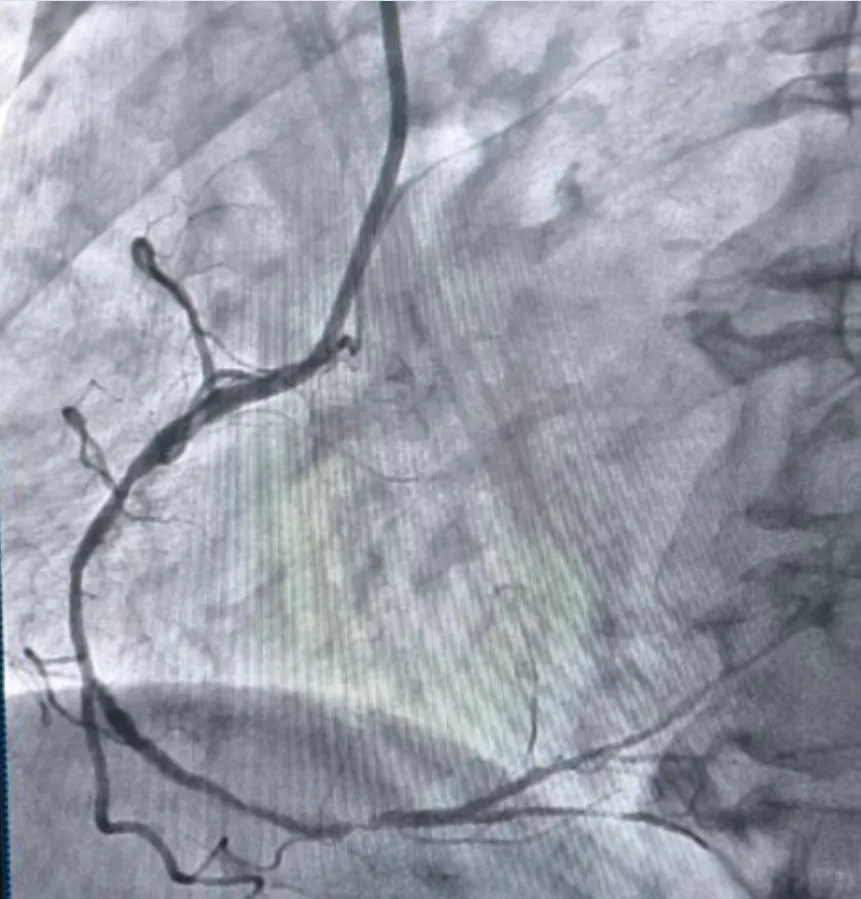

У Тернопільській обласній клінічній лікарні вперше в області провели високотехнологічну процедуру ротаційну атеректомію.

Йдеться про складне втручання, яке застосовується у випадках вираженого кальцинозу коронарних артерій, коли стандартні методи не дають результату, пише “Перший Онлайн”.

За словами завідувача відділенням інтервенційної радіології, кардіології та реперфузійної терапії Богдана Маслія, у пацієнтки діагностували значне звуження правої коронарної артерії. Розширити її традиційним способом – шляхом роздування балона, не вдалося, навіть із використанням балона високого тиску до 25 атмосфер (це приблизно у десять разів більше, ніж тиск в автомобільному колесі).

У таких ситуаціях на допомогу приходить ротаблятор – спеціальний пристрій із буром, покритим діамантовим напиленням. Він дозволяє «модифікувати» кальциновану атеросклеротичну бляшку, фактично шліфуючи її та відновлюючи можливість для подальшого стентування судини. Саме таким методом лікарям вдалося ліквідувати перешкоду в артерії та успішно імплантувати стенти.

«Це втручання стало важливим кроком для нашої лікарні та всієї області. Ротаційна атеректомія застосовується у найскладніших випадках кальцинованих уражень коронарних артерій, коли стандартна ангіопластика неефективна. Виконання такої процедури означає, що пацієнти Тернопільщини можуть отримати сучасну високоспеціалізовану допомогу без необхідності їхати в інші регіони», – наголосив Богдан Маслій.